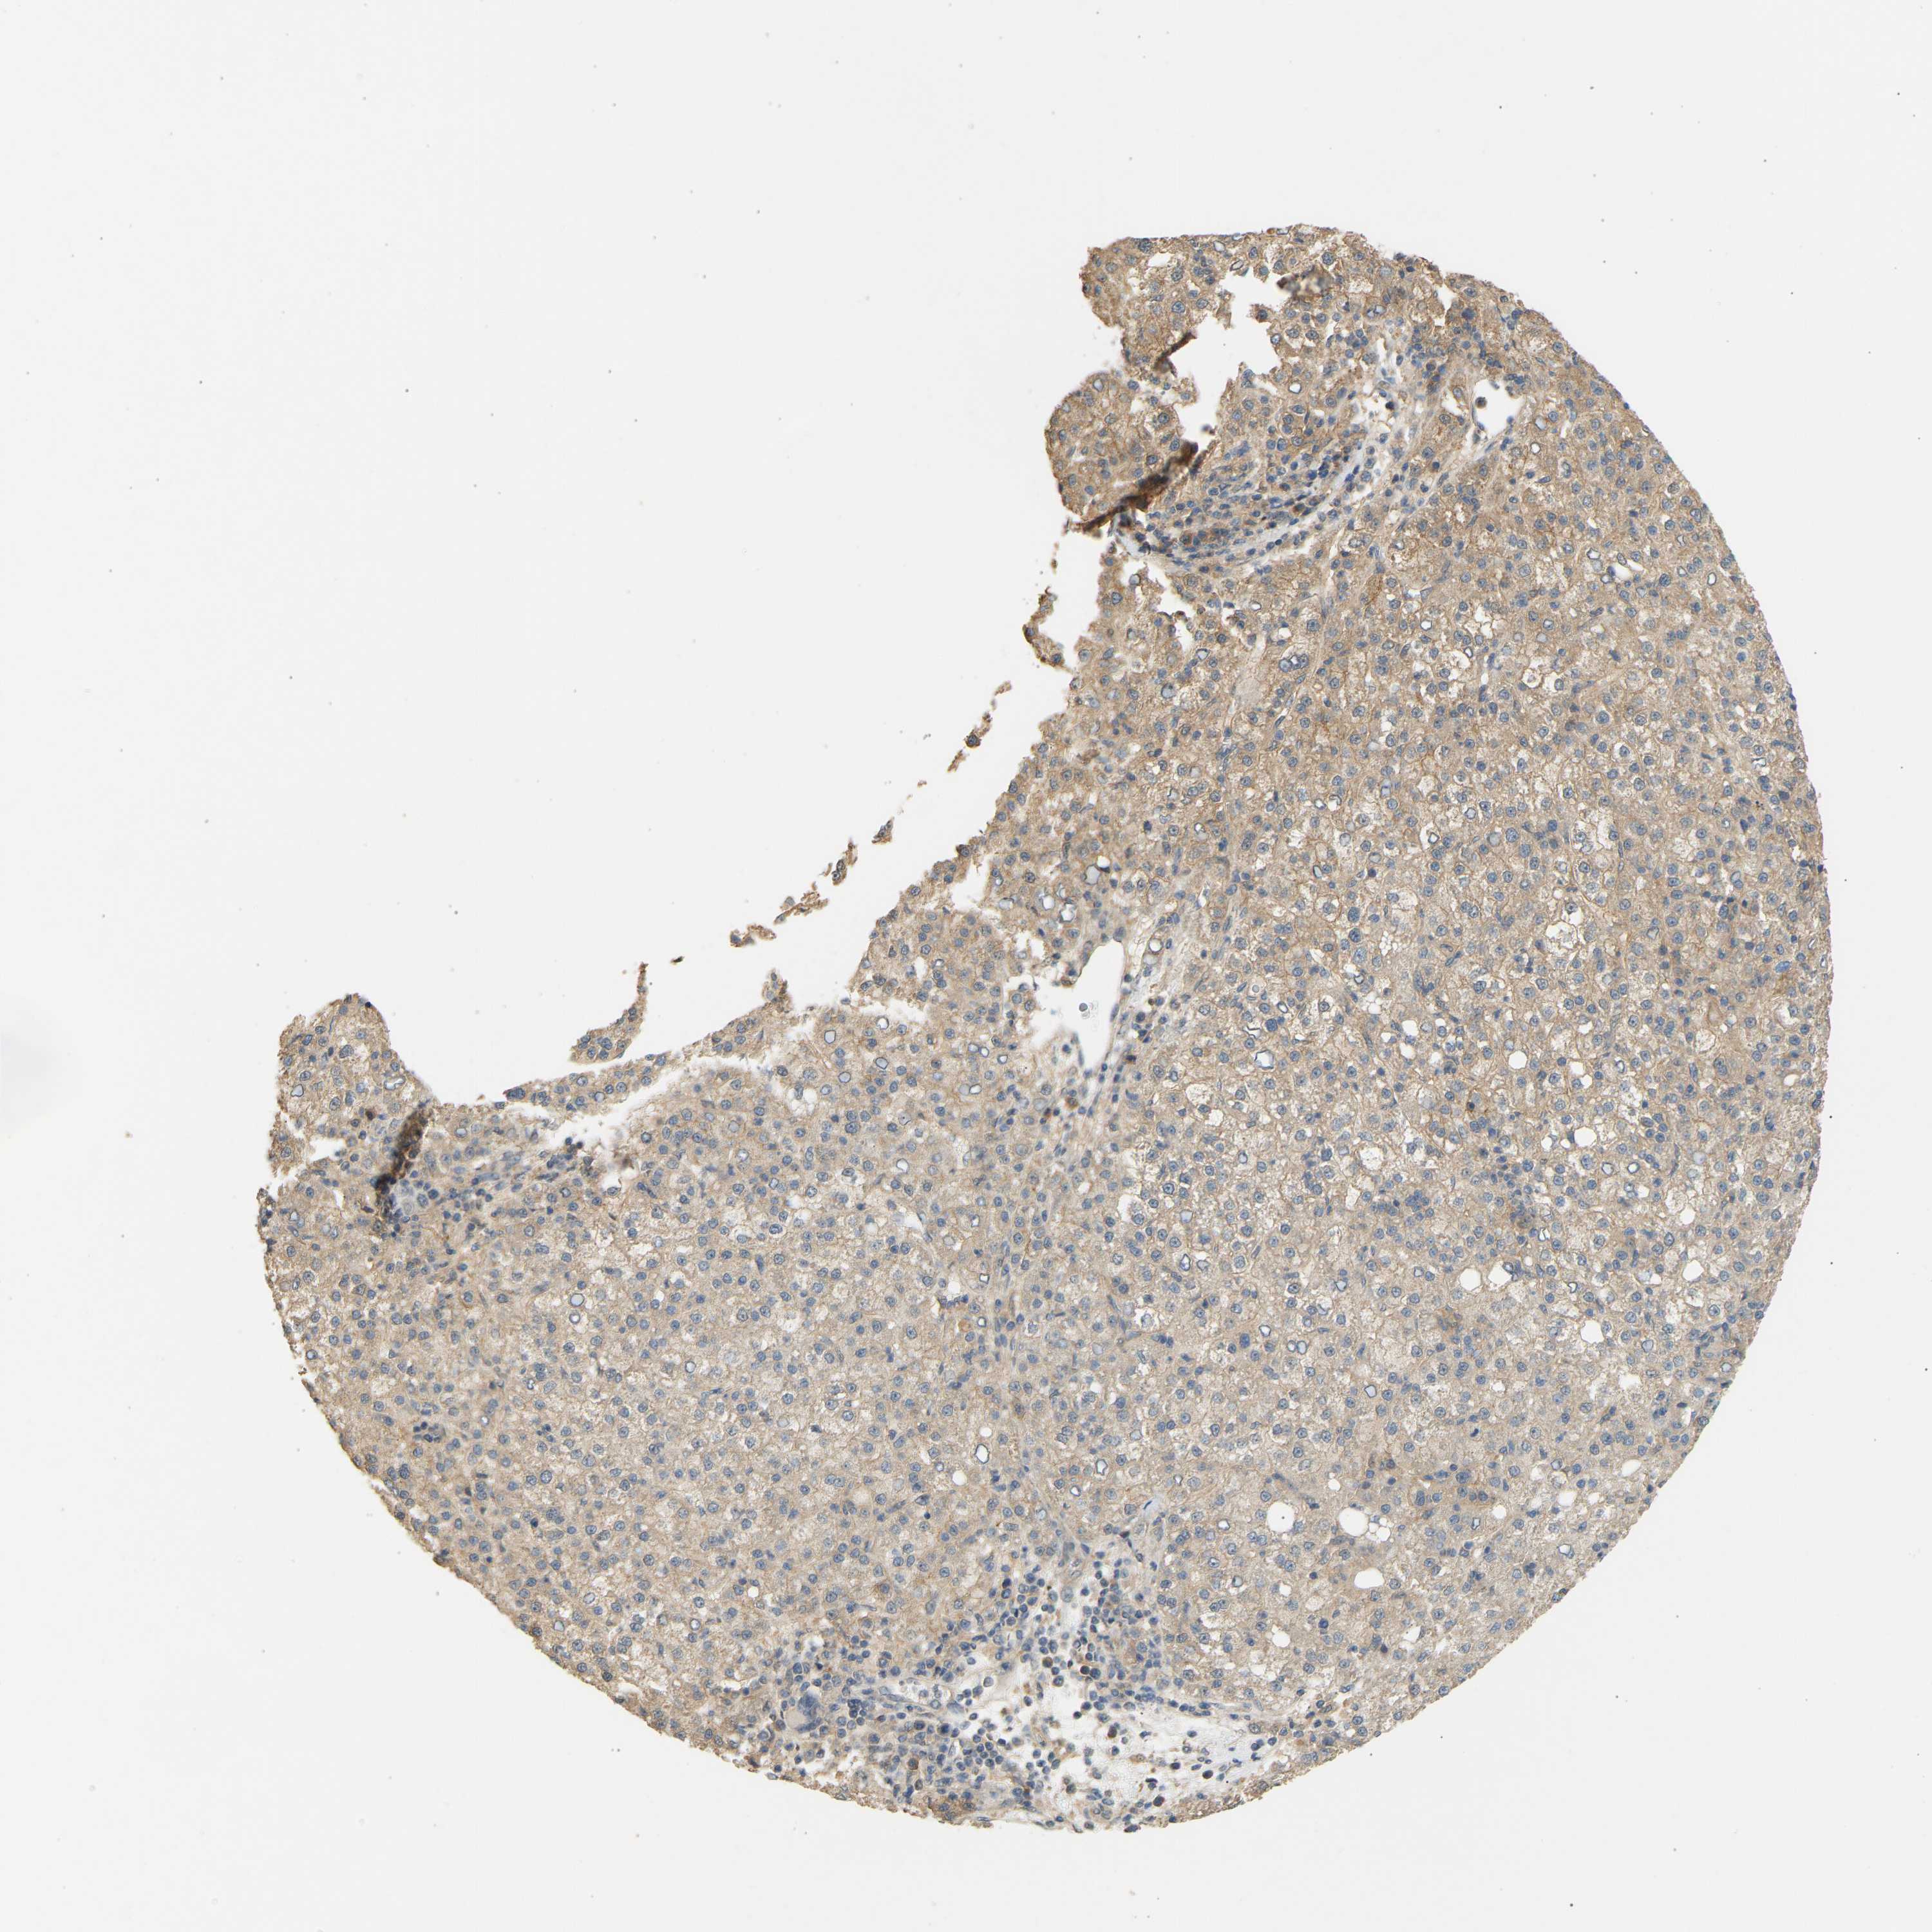

LIVER CANCER - Protein expressioni

A mouse-over function shows sample information and annotation data. Click on an image to view it in a full screen mode. Samples can be filtered based on level of antibody staining by selecting one or several of the following categories: high, medium, low and not detected. The assay and annotation is described here.

Note that samples used for immunohistochemistry by the Human Protein Atlas do not correspond to samples in the TCGA dataset.

Antibody stainingi

Antibody staining in the annotated cell types in the current human tissue is reported as not detected, low, medium, or high, based on conventional immunohistochemistry profiling in selected tissues. This score is based on the combination of the staining intensity and fraction of stained cells.

Each image is clickable and will lead to virtual microscopy that enables deeper exploration of all samples and also displays staining intensity scores, fraction scores and subcellular localization as well as patient and tissue information for each sample.

Antibody HPA019788

Staining

High

Medium

Low

Not detected

Intensity

Strong

Moderate

Weak

Negative

Quantity

>75%

75%-25%

<25%

None

Location

Nuclear

Cytoplasmic/membranous

Cytoplasmic/membranous,nuclear

Carcinoma, Hepatocellular, NOS

Cholangiocarcinoma